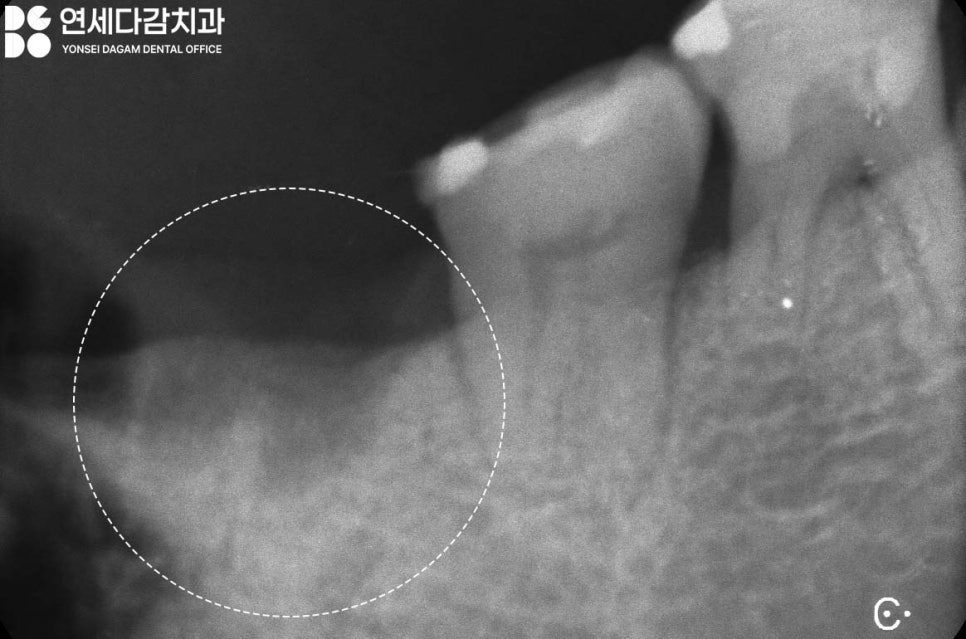

마찬가지로 심한 교모로 파절된

사랑니 부위는 끝에 위치해 있어

관리가 어렵습니다.

실제 구강 위생 환경이

좋은 편이 아니었었기에,

이런 점을 고려하여

장기적인 예후를 생각했을 때

똑같은 크라운 치료를 하는 것보다

위아래 사랑니를 모두 빼는 것이

구강 건강에 더 바람직할 때가 있습니다.